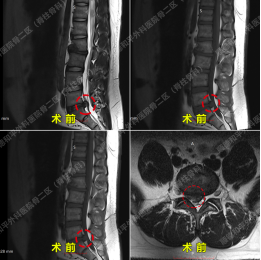

案例二:单侧双通道内镜技术(UBE)——精准解决复杂腰椎问题25岁陈嘉聪,因“陈旧性腰椎骨折”导致“腰痛伴右下肢放射性麻木半年余”,曾尝试多种保守治疗效果不佳。术前诊断显示L5/S1椎间盘脱出伴神经根病、椎管狭窄及退行性病变。张哉炯团队采用“单侧双通道内镜技术(UBE)”,通过双通道内镜精准定位,经皮椎间孔镜下完成髓核摘除术。

手术仅耗时1小时40分钟,术后第一天患者腰痛及下肢麻木明显减轻,住院4天后顺利出院。张哉炯主任同步指导术后康复锻炼,助力患者快速回归工作与生活。技术亮点:UBE技术创伤小、出血少,通过双通道扩大操作视野,适用于复杂椎间盘突出、椎管狭窄等病例,尤其适合年轻患者或需保留脊柱运动功能者。